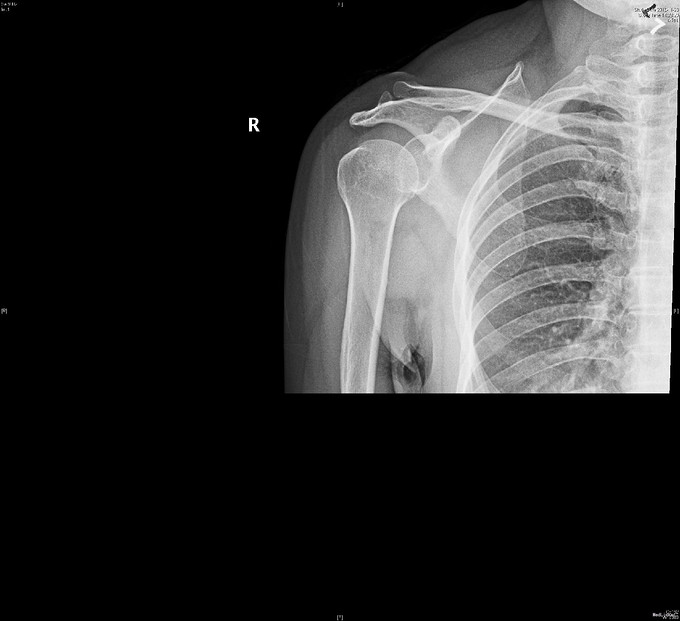

主诉:右肩疼痛5月,加重伴活动受限2月余。 现病史:患者,女性,45岁。5月前无明显诱因下出现右肩关节疼痛不适症状,偶伴有夜间痛,经休息等保守治疗后现疼痛症状略缓解。后患者至外院就诊,予口服药物等保守治疗,效果不佳,且有加重趋势。2月余前患者自觉右肩疼痛较前明显,伴活动受限。外院行MRI检查示:右肩关节内积液、右肩峰骨质增生、右肩袖肿胀、右肩盂唇信号异常。后患者来我院就诊,查右肩X线示:右肩峰前外侧见一骨性突起。门诊结合病史及体征,诊断“右肩峰下撞击综合症、右肩峰占位”收入院,行进一步治疗。

查体:右肩关节周围肌肉萎缩,右肩周压痛(+),右肩前方压痛(+),无明显肿胀。右肩关节主被动活动度明显受限,Hawking征(+),Neer征(+),Jobes征(-),Speed(+),O’brein征(-),Drop Arm(-)、熊抱试验(-)。外展肌力(Ⅳ)级。双上肢感觉正常。 辅查:见现病史,图片见下。

入院诊断:右肩峰下撞击综合症、右肩峰占位 治疗:右肩关节镜下肩峰成形,占位切除术